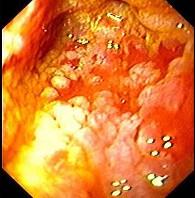

男性,67岁,反复上腹饱胀不适2年,以餐后为甚,伴反酸、嗳气、食欲不振、恶心、呕吐等。胃镜检查胃窦粘膜见散在灰白色斑块,如图:该病人最可能的诊断是 ( )...

问题 男性,67岁,反复上腹饱胀不适2年,以餐后为甚,伴反酸、嗳气、食欲不振、恶心、呕吐等。胃镜检查胃窦粘膜见散在灰白色斑块,如图:该病人最可能的诊断是 ( )

选项 A、胃泌素瘤 B、消化性溃疡 C、慢性浅表性胃炎 D、慢性萎缩性胃炎伴肠上皮化生 E、胃黄斑瘤

答案 D